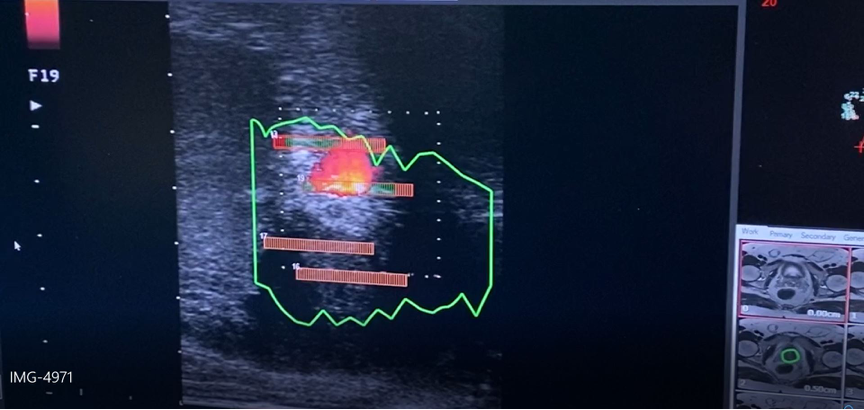

«Σε σχέση με άλλους τύπους λέιζερ απορροφάται καλύτερα από τον προστατικό ιστό και πολύ γρήγορα, μειώνοντας σημαντικά το χρόνο επέμβασης αλλά επιτρέπει και την διαδερμική με βελόνα εφαρμογή στην περιοχή του περινέου (δηλ. μεταξύ των όρχεων και του πρωκτού) χωρίς να χρειάζεται να εισέλθει δια μέσω της ουρήθρας. Αυτό σημαίνει ότι κάλλιστα μπορεί να εφαρμοσθεί μόνο με τοπική αναισθησία», επισημαίνει ο κ. Νικόλαος Μερτζιώτης, Χειρουργός, Ουρολόγος – Ανδρολόγος, Διδάκτωρ Πανεπιστημίου Αθηνών, Μετεκπαιδευθείς στο UCL της Μεγάλης Βρετανίας, Διευθυντής Ουρολογικής Κλινικής, Επανορθωτικής και Χειρουργικής Ανδρολογίας του Metropolitan General.

Με την ίνα του λέιζερ καταστρέφεται ο υπερπλαστικός ιστός του προστάτη, ενώ τις επόμενες ημέρες συνεχίζεται η καταστροφή δια μέσω της φυσιολογικής διαδικασίας που ονομάζεται πηκτική νέκρωση έτσι ώστε ακόμα μεγαλύτερη ποσότητα προστατικού ιστού να νεκρώνεται, επιτρέποντας την καλύτερη ούρηση.

Η εστιακή θεραπεία με φωτοεξάχνωση (laser)